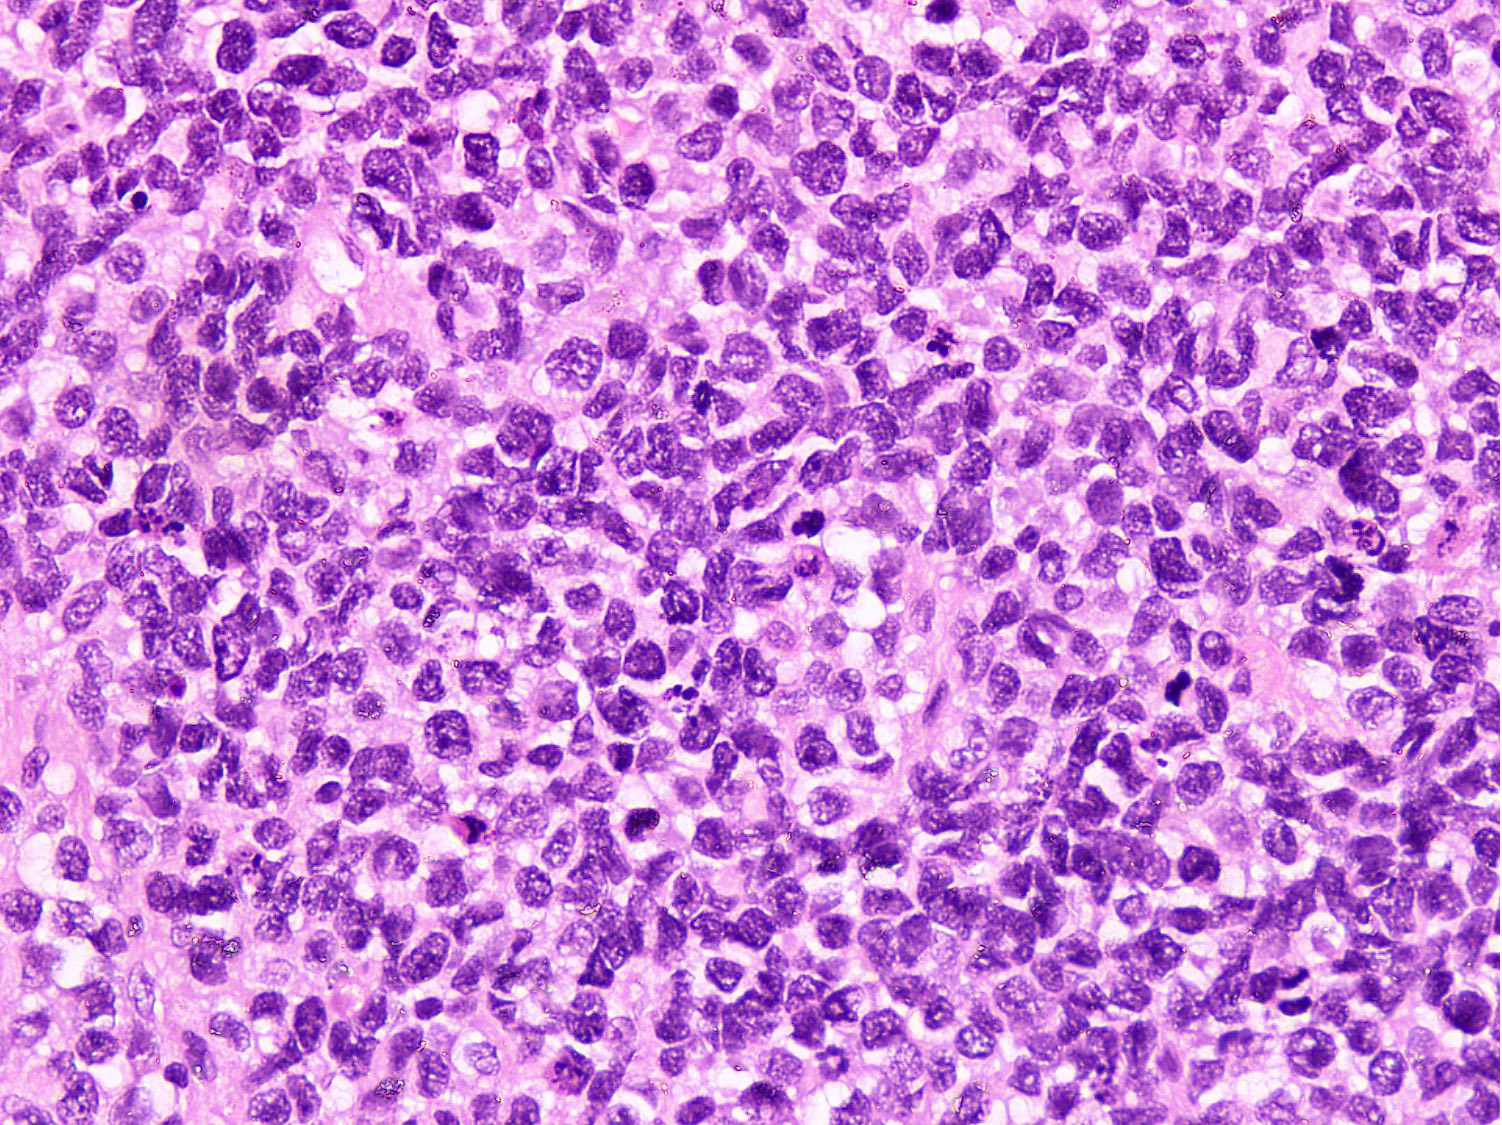

Microscopic (histologic) description

- Cellular round cell tumor

- Large clusters, nests, cords and trabeculae of primitive round cells, separated by variably thick fibrovascular septa

- Loss of cellular cohesion in the center forms alveolar-like, cystic and vague papillary appearance (Histopathology 2022;80:98)

- Layer of cells adheres to the periphery of the spaces and fibrous septa

- Small to intermediate sized monomorphic cells with scant cytoplasm

- Hyperchromatic nuclei with variable conspicuous small nucleoli

- Cells in the center have poor preservation and are necrotic; may appear floating

- Multinucleated tumor giant cells with wreath-like lineup of nuclei are common (Acta Pathol Microbiol Immunol Scand A 1982;90:345)

- Round to oval rhabdomyoblasts with abundant acidophilic cytoplasm may be present

- Brisk mitosis and variable tumor necrosis

- Occasional cases may show clear cell morphology with pale, glycogenated cytoplasm

- Rare anaplasia

- Some cases may show histologic features of embryonal rhabdomyosarcoma; molecular studies are essential to characterize such cases (Am J Clin Pathol 2013;140:82)

- Solid variant:

- Sheets of neoplastic cells

- Lack fibrovascular septa, pseudoalveolar spaces and dyscohesion (Cancer Genet Cytogenet 2005;163:138)

- May show rhabdomyoblastic differentiation

- Abundant mitotic activity

Microscopic (histologic) images

Contributed by Nasir Ud Din, M.B.B.S.